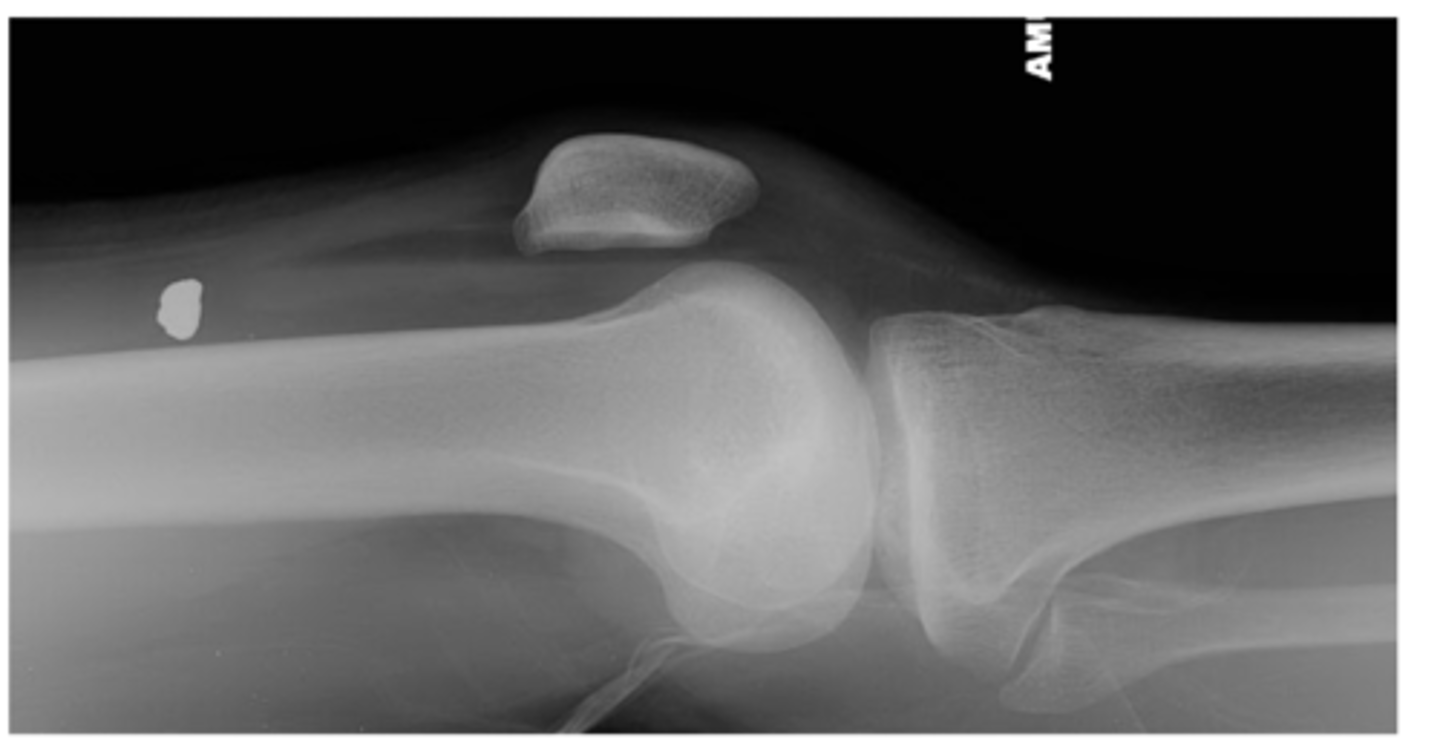

1. Muscles - atrophy - swelling (ex: swelling around the knee joint as seen in this image)